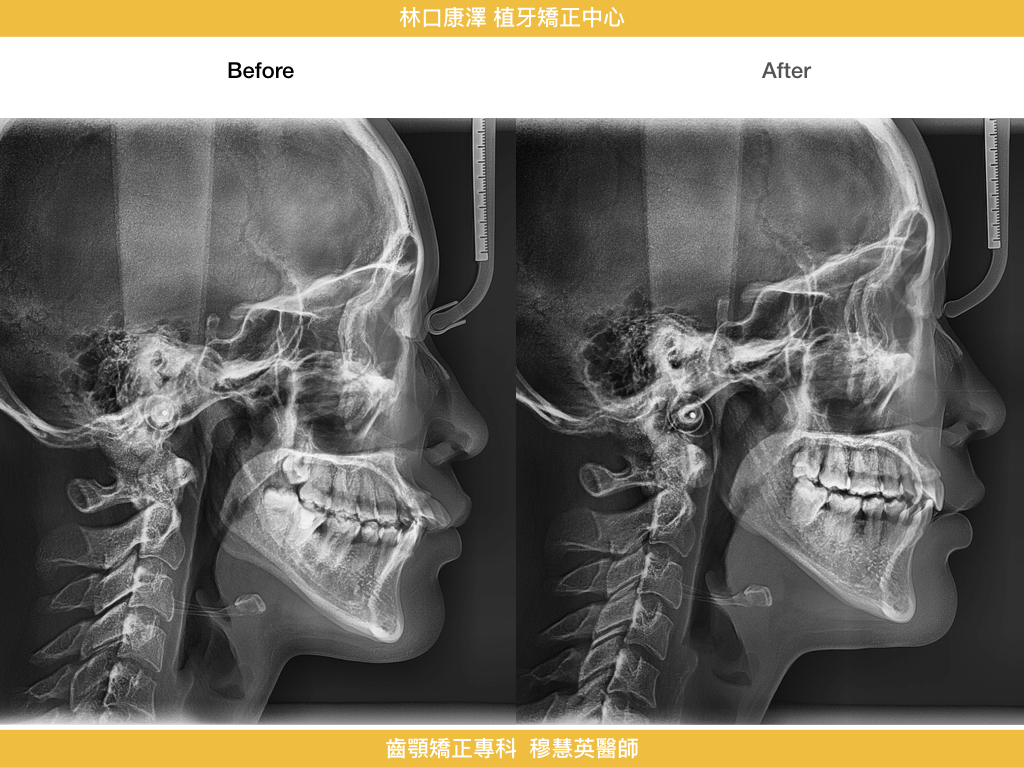

暴牙、智齒取代、拔牙-隱適美

以下展示完成案例